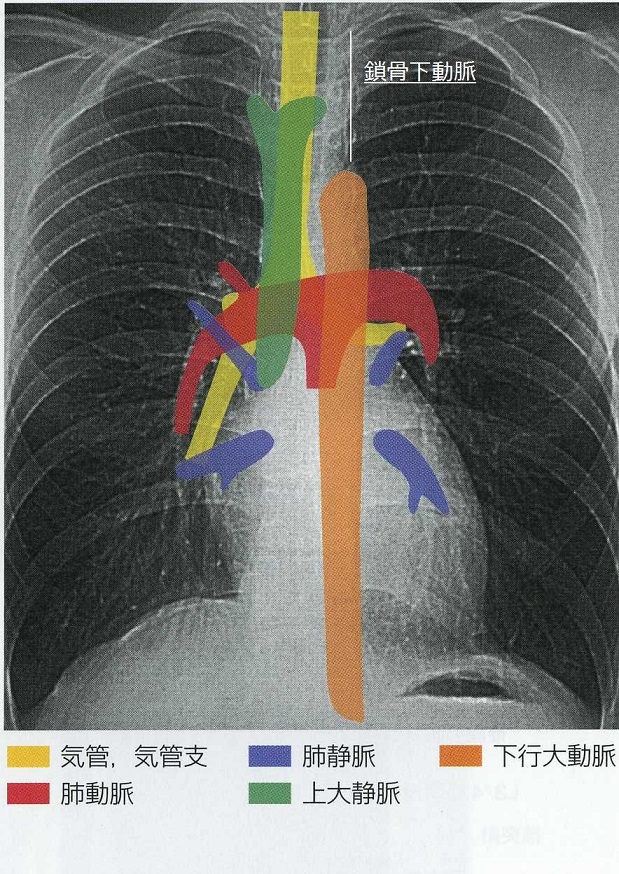

4. 気管・気管支、大動脈、肺動脈や縦隔線を確認していく。この際シルエットサインにも注意して診ていく。

胸部レントゲンに写る臓器